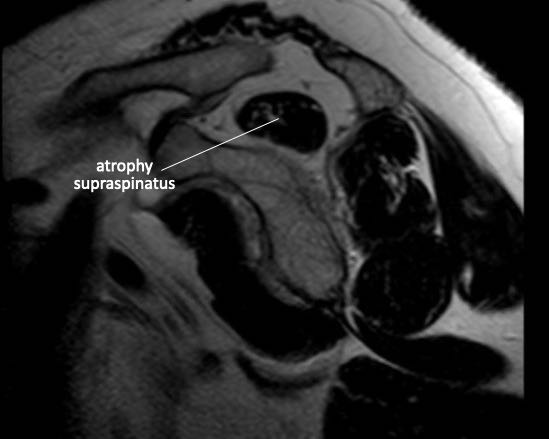

Teo cơ – Dấu hiệu tiếp tuyến (Tangent sign)

Phương pháp đánh giá teo cơ của Warner dựa trên hình ảnh mặt phẳng chéo đứng dọc (oblique sagittal) ở vị trí trong so với mỏm quạ.

Một đường thẳng được vẽ từ bờ mỏm quạ đến đỉnh dưới của xương bả vai, và từ gai xương bả vai đến mỏm quạ.

Nếu cơ lồi lên trên đường này, không có teo cơ.

Nếu cơ nằm ngay dưới đường này, có teo cơ mức độ vừa.

Nếu hầu như không thấy cơ, có teo cơ mức độ nặng.

Hình bên trái cho thấy giải phẫu cơ bình thường trên ảnh mặt phẳng đứng dọc.

Hình bên phải là của bệnh nhân có rách toàn bộ chiều dày cả gân cơ trên gai và gân cơ dưới gai kèm co rút.

Có hình ảnh teo mỡ của cơ trên gai và cơ dưới gai.